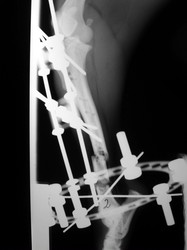

Fijación Externa

PRÁCTICAS CURSO DE FIJACIÓN EXTERNA PERFECCIONAMIENTO.

Híbrido.